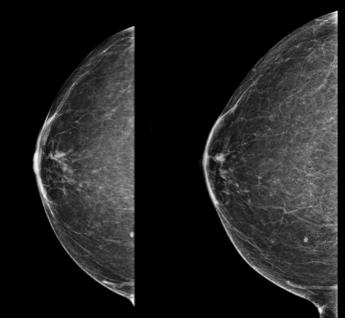

Thursday morning began with a warm welcome by Dr. Linda Moy, followed by an insightful lineup of sessions highlighting updates on screening techniques and modalities. Drs. Supriya Kulkarni and Katy Lowry provided an update on digital mammography and digital breast tomosynthesis, offering insights into recent evidence and ongoing screening trials. Dr. Jessica Leung discussed the benefits and drawbacks of supplemental screening ultrasonography. Drs. Habib Rahbar and John Lewin brought to the stage the debate that many breast imaging radiologists have had within their practices: whether to initiate an abbreviated magnetic resonance imaging (MRI) or contrast-enhanced mammography (CEM) program. Drs. Rahbar and Lewin put these modalities head to head, with compelling evidence for both.

Throughout the week, there was a consistent focus on mammography screening and supplemental screening. Expanding on the topic of surveillance, Drs. Janie Lee and Wendie Berg discussed how early detection of second breast cancer in patients with a personal history of breast cancer is essential to improving survival. They discussed data on surveillance outcomes and the recommendation for annual MRI in patients with a personal history of breast cancer before age 50 years and patients with dense breast tissue. Dr. Berg highlighted that MRI might not be accessible or the most suitable choice for certain individuals. She introduced evidence supporting CEM for supplemental screening in patients receiving surveillance. She discussed screening ultrasonography as a viable alternative when neither MRI nor CEM is feasible for certain individuals.